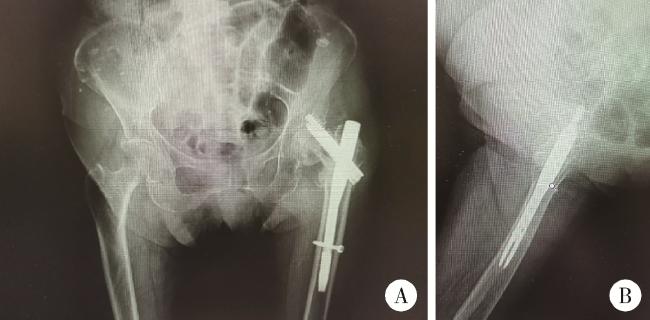

图4 患者术后16个月髋部X线片

Figure 4 Radiographic examination of the hip of patient 16 months postoperatively

A, sixteen months post-operation, X-ray imaging of anteroposterior view of hips; B, lateral view of left hip, revealed a fracture in the left femoral neck and a cut-out screw.

老年女性患者,88岁,患者2020年10月26日步行时不慎摔倒,左髋着地。于北京大学第一医院急诊查双髋X线片示左侧股骨粗隆间不稳定骨折(图 1)。查体:生命体征平稳。左髋强迫外展外旋位,左下肢短缩约2 cm。左髋局部压痛,轴向叩击痛,活动度拒查。双下肢感觉无异常,双侧足背动脉搏动可。入院后行左股骨粗隆间骨折闭合复位InterTAN髓内钉固定术,术中复位满意,过程顺利(图 2),术后复查髋关节X线片示骨折复位及内固定物位置满意(图 3)。术后次日开始骨化三醇、碳酸钙D3抗骨质疏松治疗,术后1周加用地舒单抗。术后1个半月部分负重,术后3个月可下地行走,无明显不适。2021年10月7日(术后12个月)无明显诱因出现左髋疼痛,进行性加重,逐渐出现行走困难。2022年2月28日(术后16个月)于北京大学第一医院门诊复查双髋正位X线片考虑左侧股骨颈骨折,内固定物对髋臼侧骨质有一定破坏(图 4),为行治疗收治入院。既往有高血压、腔隙性脑梗、房颤病史。查体:生命体征平稳,左髋关节周围压痛明显,无红肿,关节活动受限,疼痛明显,查体配合差。入院查血常规:白细胞计数7.1×109/L,中性粒细胞计数6.5×109/L,中性粒细胞百分比92.3%,超敏C反应蛋白4.27 mg/L,降钙素原0.02 μg/L,除外感染后行左髋关节内固定物取出加半髋关节置换术,术中未见浑浊关节液及组织液,既往股骨粗隆间骨折部位已完全愈合,新发股骨颈骨折(图 5),髋臼外上方有一处头颈螺钉切割出的缺损区,直径约1.5 cm,内有纤维瘢痕组织填充,取局部组织留取病理,送咽拭子细菌培养,培养结果阴性。术中采用骨水泥型11号股骨假体柄(长度200 mm)和外径44 mm的双极金属股骨头行半髋关节置换术,术后复查髋关节X线片(图 6),可见髋臼侧骨质密度减低。术后预防性抗感染治疗,术后1周出院,院外继续抗骨质疏松治疗。术后3个月患者反馈左髋疼痛及功能明显改善,患者及家属对治疗满意。